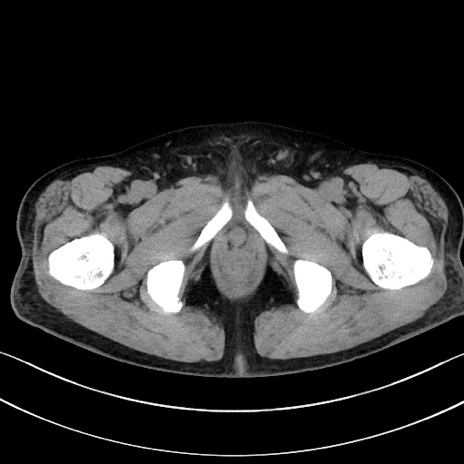

冠状断像